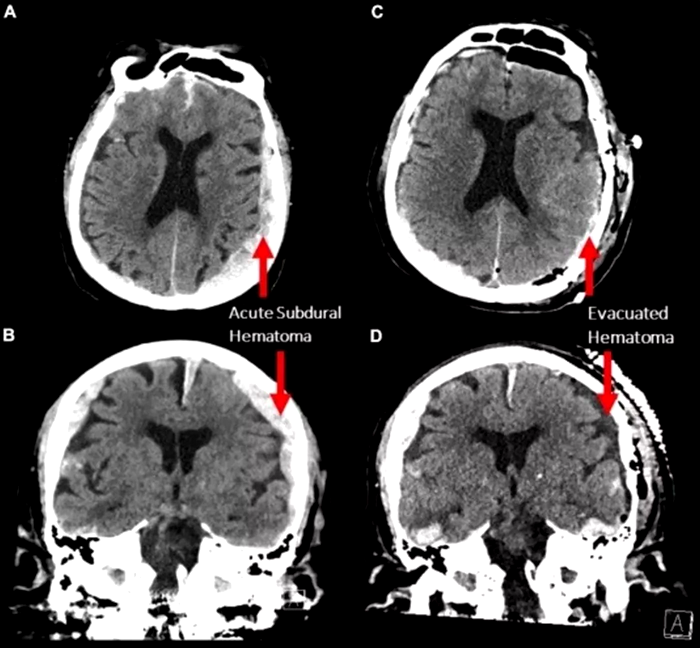

Pacientul monitorizat era un bărbat de 87 de ani care suferise o cădere și dezvoltase o formă gravă de epilepsie. În timpul spitalizării, a fost conectat la un EEG (electroencefalograf) pentru a i se studia activitatea cerebrală. În mod neașteptat, pacientul a suferit un stop cardiac în timpul investigației.

Totuși, cercetătorii atrag atenția că studiul se bazează pe un singur caz, iar pacientul avea leziuni cerebrale preexistente. Prin urmare, este nevoie de mai multe cercetări pentru a stabili dacă acest tip de activitate cerebrală este comun tuturor oamenilor.